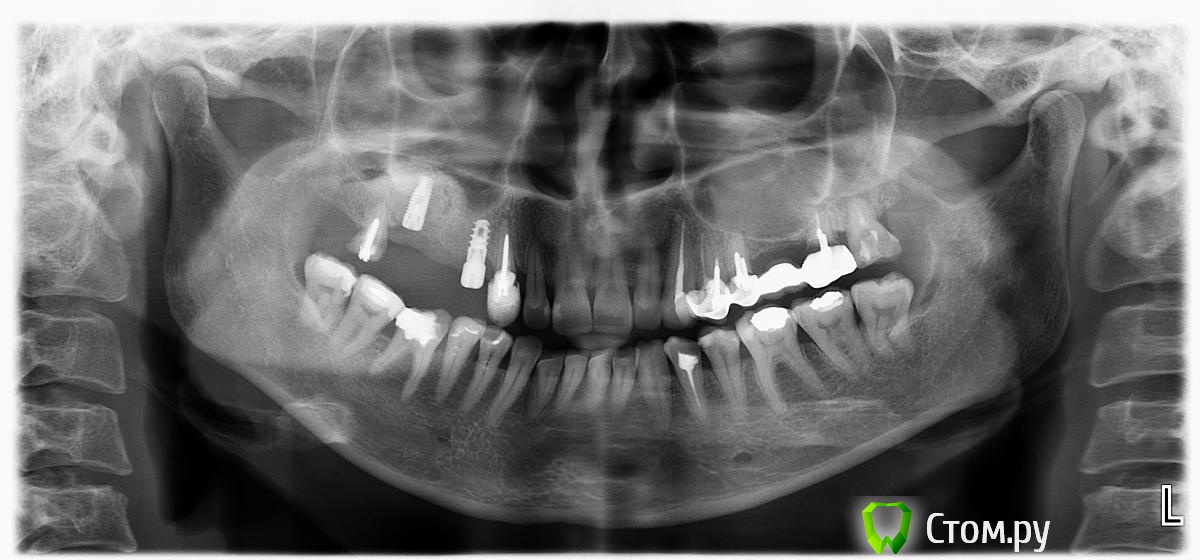

Dc.Petrov Опубликовано 16 апреля, 2014 Автор Поделиться Опубликовано 16 апреля, 2014 спустя полгода все получилось.И все таки зря я не пошел крестально изначально...Сейчас с 2х сторон отслаивался, небную стенку отслоил через гребень Ссылка на комментарий